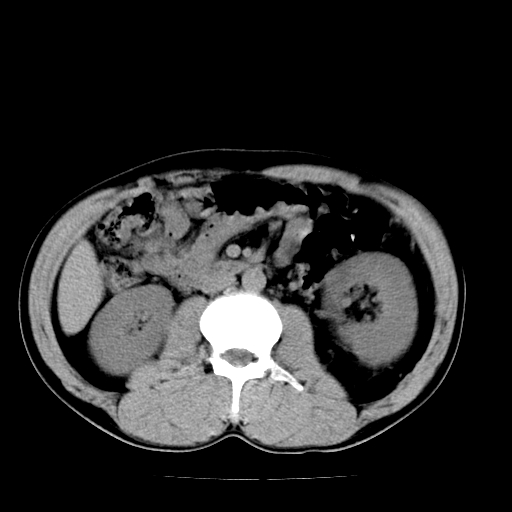

以下是引用天南地北在2007-4-30 13:36:00的发言:[br]支持慢性胰腺炎伴有假性囊肿

以下是引用andymaomao在2007-4-30 14:28:00的发言:[br]支持:1.慢性胰腺炎并假性囊肿形成可能;[br] 2.左肾形态稍增大,旋转不良。